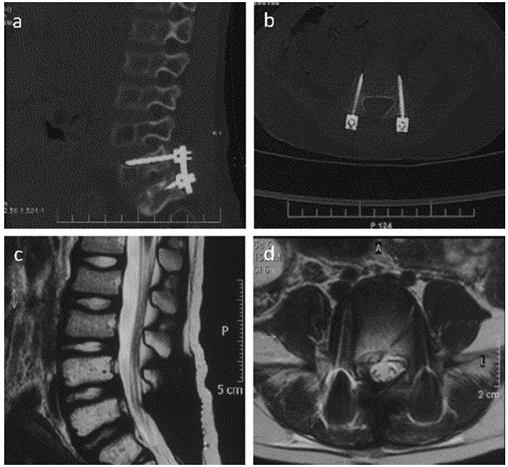

在显微镜下进行肿瘤根治性切除,并在L5和S1处植入双侧椎弓根螺钉。患者术后肌肉力量有所改善,可以独立行走,进一步接受全身化疗(长春新碱+环磷酰胺+阿霉素/异环磷酰胺+依托泊苷)和160cGy单次骨盆照射28天。术后1周和1年的随访CT(图2a,b)和MRI(图2c,d)结果显示,肿瘤没有明显复发。

图2. 术后1周和1年的随访CT(图2a,b)和MRI(图2c,d)